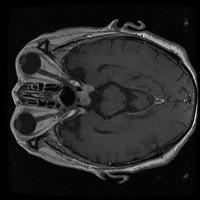

tumor otak Computer Vision Project

Here are a few use cases for this project:

Medical Diagnostics: This model can be used for assisting healthcare professionals in diagnosing brain tumors by classifying them into glioma, pituitary, or meningioma, which can save time and lead to early and accurate disease diagnosis.

Health Monitoring Software: It can be implemented in health and wellness apps to monitor a patient's MRI scans regularly, thus providing an early warning system for possible tumor growth.

Training medical students and resident doctors: The model can be used as a training tool for medical students and resident doctors to better understand and identify different types of brain tumors from MRI images.

Research Studies: It may be used by scientists and researchers for creating more focused and comprehensive studies on brain tumors, contributing to advancements in the respective field of study.

Telemedicine: This model can be helpful in telemedicine portals where expert opinion may be lacking. The model could provide initial diagnosis based on MRI scans before a patient consults with a healthcare professional.